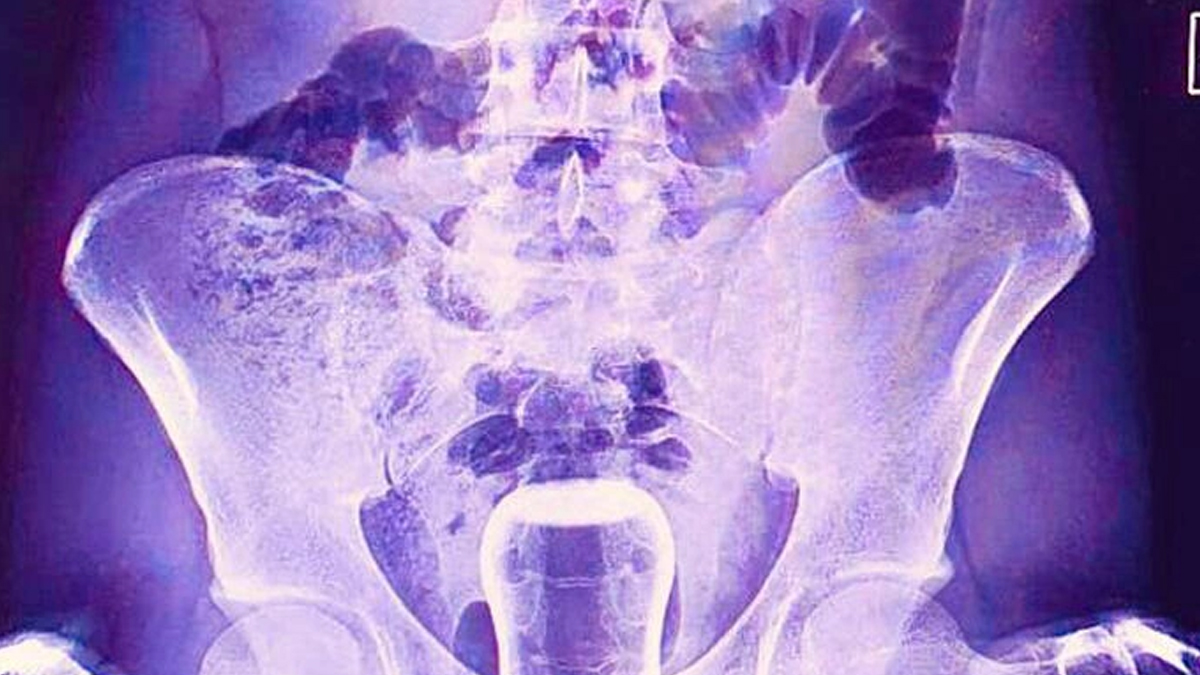

Şanlıurfa'da ismi açıklanmayan bir kişi Mehmet Akif İnan Eğitim ve Araştırma Hastanesin'e başvurdu. Acil serviste hastanın çekilen röntgeninde anüs bölgesinde çay bardağı görüldü. Bu kişi genel cerrahi servisinde ameliyata alındı. Çay bardağı, uzman doktorlar tarafından gerçekleştirilen operasyonla çıkarıldı.

Ameliyatla sancıdan kurtulup eski sağlığına kavuşan hasta doktorlara, uzun zamandır basur hastası olduğunu, hacamatçıya gittiğini ve yağlı çay bardağın kazayla anüs bölgesine kaçtığını ileri sürerek, ameliyattan dolayı teşekkür etti.